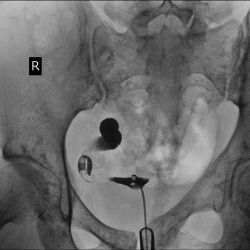

Мужчина 36 лет .Состояние после дробления камней.

Подскажите место нахождения конкремента ?? Я думаю в лоханке, так как почка опущена?